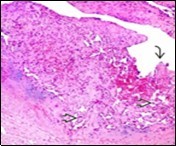

On microscopy, superficial squamous epithelial surface is intact. Sub-epithelial connective tissue stroma exhibits slit-like, vascular spaces. Upon extended magnification, multiple, intravascular papillary projections encompassed within a hyalinised stroma are discerned. Centroidal calcification appears in combination with intravascular, papillary endothelial cell proliferation, lined with singular layer of endothelial cells devoid of cytological atypia6, 7.

Characteristically, the vascular neoplasm denominates numerous papillae within blood vessels. Papillae are coated with singular or dual layer of flattened endothelial cells with an encompassing hyalinised, fibrous tissue core. Vascular lumen is distended with thrombosis. Foci of haemorrhage with fibrinous and purulent exudate are discerned. Tumour perimeter depicts inflammatory granulation tissue. Cholesterol clefts and focal reactive bone formation may concur. Extraneous squamous epithelium may be discontinuous and ulcerated. The neoplasm is devoid of features of malignancy4, 6.

Numerous micro-calcifications can be observed within the lesion which may engender vascular occlusion and tissue necrosis6. Figure 1, Figure 2, Figure 3, Figure 4, Figure 5, Figure 6, Figure 7, Figure 8.

Figure 4.Papillary endothelial hyperplasia enunciating papillary arrangements coated with single layer of endothelial cells intermingled with significant fibrinous and thrombotic exudate13.